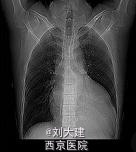

体格检查在左侧第三肋间闻及 3/6 级的「拉锯样」杂音。胸片检查发现心影增大,心电图显示完全左束支传导阻滞伴频发室早。经胸壁心脏超声显示左心室极度扩大,左心室舒张末期容积为 472 ml,射血分数(EF)为 20%。